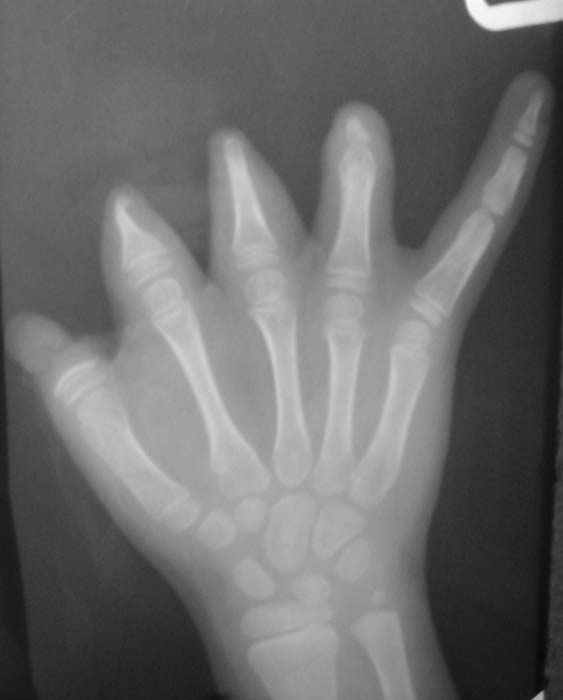

Уважаемые коллеги!Девочка, 6 лет. Врожденная аномалия развития кистей и стоп.Вопрос: лечение?В приложении - рентгенограммы и клинические фотографииЗаранее благодарен!С уважением,А.В.Владзимирский

Безусловно девочке необходимо создать 1-й палец правой кисти - создать противопоставление остальным пальцем и таким образом получить функцию захвата. Варианты операций:

1. Пересадка 2-го пальца стопы (предварительно сделав доплерографию стопы и кисти)

2. Транспозиция культи 3 или 4-го пальца в положение 1-го.

3. Несвободная пересадка комплекса тканей на a. radialis в который входит участок лучевой кости (реверсионный лучевой лоскут с костным фрагментом для восстановления 1-го пальца.

4. Возможна свободная костная пластика (например, фрагмент в/3 большеберцовой кости кости с одновременной кожной пластикой по Блохину-Конверсу.

В каком состоянии сейчас находится сухожильно-мышечный аппарат правой кисти?

Обратите внимание на культю 2-го пальца - может необходимо резецировать острый костный конус с пластикой кожи над ней?